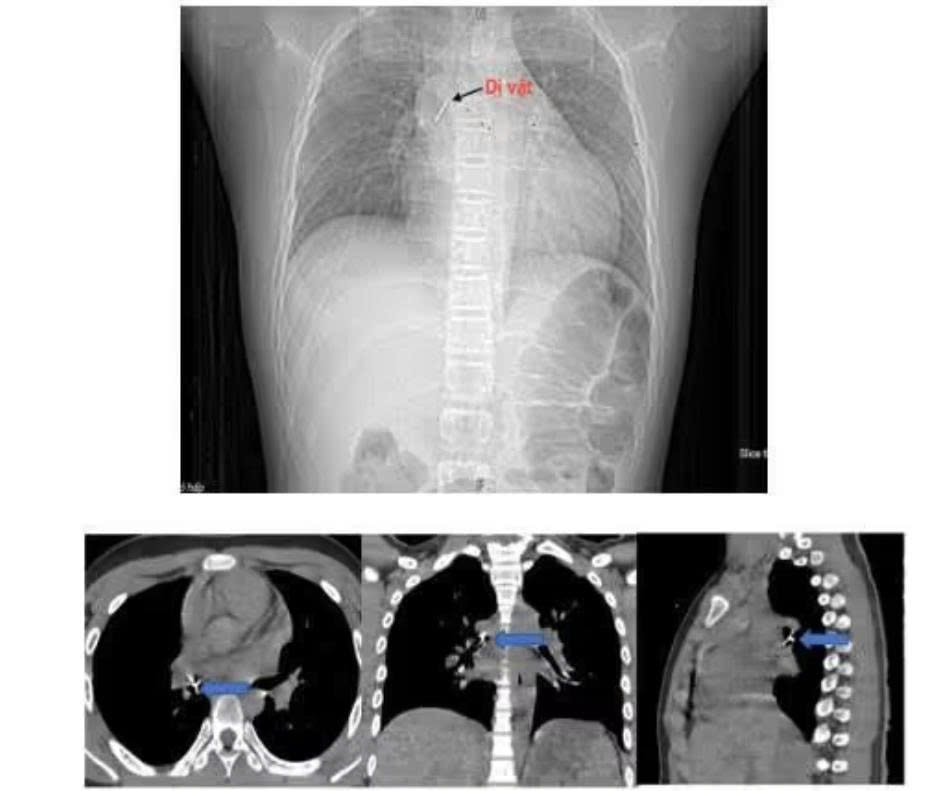

Ngay lập tức, gia đình đưa bé tới bệnh viện gần nhà. Sau chẩn đoán bằng chụp cắt lớp vi tính lồng ngực và nội soi phế quản ống mềm, các bác sĩ xác định dị vật nằm sâu tại phế quản trung gian bên phải, đầu ghim đã đâm xuyên vào thành phế quản gây chảy máu và phù nề.

Sau hơn hai giờ can thiệp tại cơ sở ban đầu không thành công, bệnh nhi được chuyển khẩn cấp tới Bệnh viện Phổi Trung ương. Tiếp nhận ca bệnh, ThS.BSCKII Nguyễn Lê Nhật Minh - Trưởng khoa Nội soi chẩn đoán và can thiệp cùng ê-kíp đã tiến hành nội soi phế quản ống mềm để gắp dị vật.

Theo bác sĩ Minh, dị vật là chiếc đinh ghim sắc nhọn, đầu ghim cắm sâu vào thành phế quản, thao tác lấy rất khó bởi bệnh nhi có phản xạ ho, cần thao tác nhanh, chính xác để tránh làm rách thành phế quản hoặc đẩy dị vật xuống sâu hơn, có thể gây nhiễm trùng, tràn khí màng phổi hoặc suy hô hấp cấp.

Ê-kíp đã cẩn trọng dùng kìm nội soi chuyên dụng gỡ phần đầu ghim khỏi thành phế quản, sau đó từ từ gắp cả dị vật ra ngoài. Toàn bộ thủ thuật diễn ra trong khoảng 15 phút và thành công.